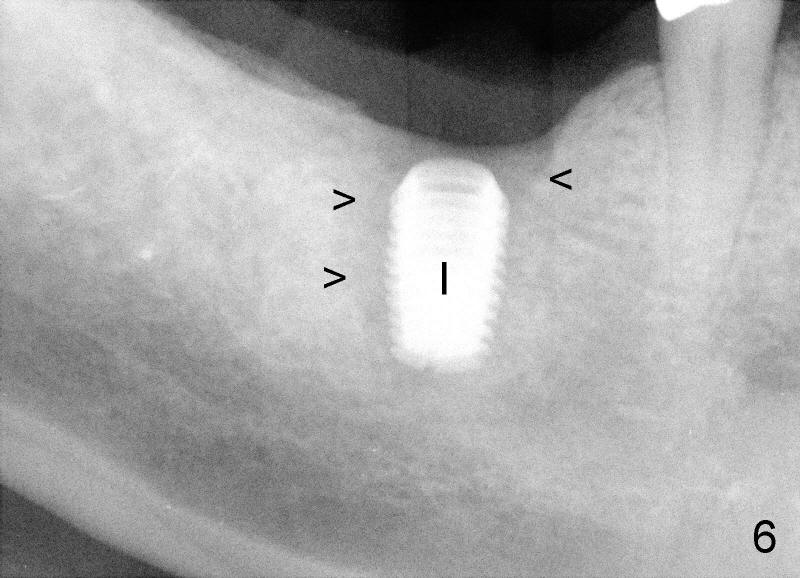

Unfortunately, there is bone resorption around the implant 3 months postop (Fig.6: >, as compared to Fig.4). Granulation tissue is present over the implant (Fig.7 *). The patient complains occasional pain and swelling after implant placement. Bone resorption is confirmed after removal of granulation tissue around the implant (Fig.8 *). After acid etch, Endogain (Fig.9 *, Straumann) is placed around the implant (P: healing plug). Flaps are approximated with 4-0 plain gut suture. Collagen membrane should have been used. Amoxicillin is prescribed, but the patient does not take it. It appears that bone graft to the sockets of #19 helps form an apparently continuous bone plate at the alveolar crest over the mesial (M in Fig.6') and distal (D) sockets, as compared to Fig.4'.

Three months later, the wound heals. X-ray shows that bone loss distal to the implant (Fig.6 double arrowheads) disappears, similar to the one taken another two months later (Fig.10), when the implant is uncovered. The circumferential bone loss shown in Fig.8 is reduced to the distal crest of the implant at the time of uncovering (data not shown).